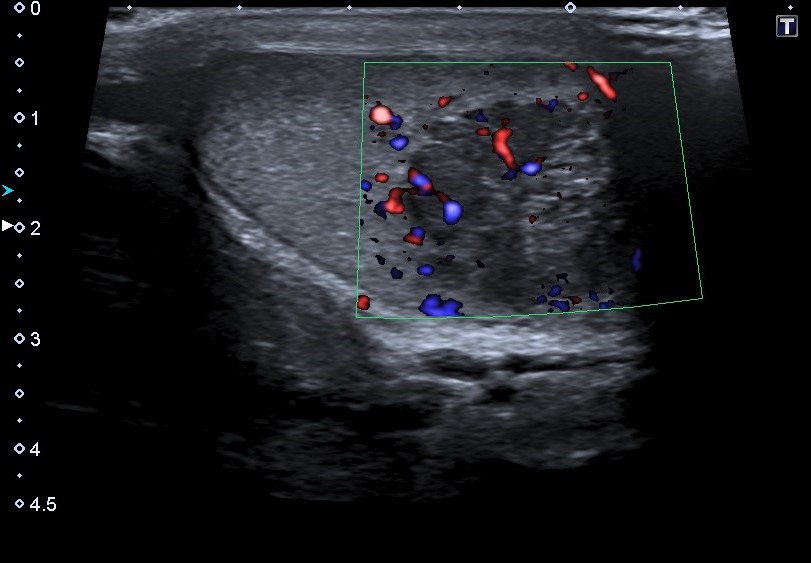

Hallazgos ecográficos

Ecografía escrotal: En testículo derecho se aprecia lesión heterogénea de predominio hipoecogénico con alguna calcificación grosera, polilobulada, de bordes mal definidos, con medidas aproximadas de 36 mm de diámetro máximo, con vascularización en su interior en el registro Doppler, sugestivo de proceso neoformativo testicular. No se objetiva engrosamiento epididimario ni de cubiertas escrotales.